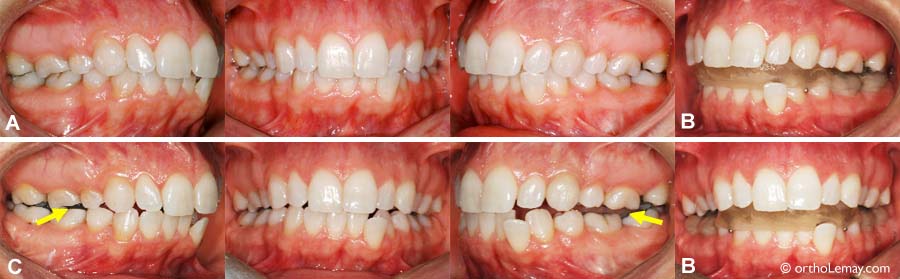

(A) Jeune femme de 26 ans se plaignant de douleurs articulaires (ATMs), céphalées et migraines depuis plusieurs années. Elle présente une malocclusion avec un engrenage inadéquat du côté droit et du chevauchement dentaire modéré.

(B) 3 semaines après le port d’une plaque occlusale inférieure les céphalées ont diminuées significativement. L’épaisseur de la plaque a été augmentée pour combler l’espace qui apparaissait progressivement entre les dents à mesure que la mandibule se repositionne vers le bas et l’arrière.

(C) Après 5 semaines, les symptômes sont pratiquement tous disparus mais, lorsque la plaque est enlevée (pour les photos), on remarque le changement important qui s’est produit; la mandibule s’est déplacée et il ne reste que des contacts entre les molaires. Une phase corrective en orthodontie (broches) sera nécessaire pour obtenir une occlusion permettant de maintenir la position mandibulaire révélée par la plaque et et une fonction adéquate.